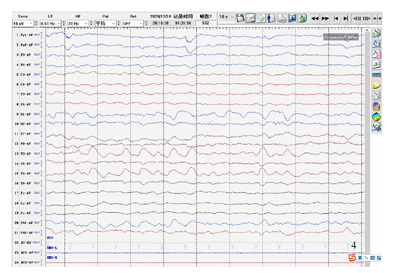

患者,女性,37岁,主因"间断抽搐发作36余年,加重5月余"于2020年11月24日就诊于河北医科大学第二医院神经内科。患者于6月龄时出现抽搐发作,表现为双眼向右上偏斜,四肢抽搐,伴意识不清,呼之不应,持续约数小时缓解。后此症状间断发作,表现同前,每次共3 h左右,发作频率约1次/20 d,共发作3次后未再发作。8月龄时出现发作性肢体活动障碍,表现为哭闹时仅一侧肢体活动,意识清楚,偏瘫侧肢体软,左右侧肢体交替发作,单侧偏瘫持续3天左右交替至另一侧,每次共持续1周左右,发作频率约半个月1次,就诊于当地医院,诊断为"低钙抽搐",给予补钙治疗,症状未见明显好转。1岁半时就诊于北京数家医院,于首都医科大学宣武医院完善头颅CT检查未见明显异常(具体不详),予以口服药治疗(具体不详),服用完后自行停药。后间断就诊于当地医院,诊断为"癫痫",15岁左右开始口服抗癫痫药物(具体不详)。11年前(26岁时)口服卡马西平0.2 g、2次/d,出现发作性肌张力障碍,表现为双上肢伸直,双手腕屈曲外旋,偶伴头眼右偏,意识清楚,为成簇发作,约半个月1簇,3~5 d/簇,数次/d,每次持续约数分钟,月经前或情绪不稳定时易发作;交替性偏瘫发作症状逐渐演变为发作时偏瘫侧肢体伴有强直性肌张力障碍,右侧肢体发作时症状常较左侧重。逐渐停用卡马西平(共服用数月),上述症状仍间断发作,发作表现及频率同前,就诊于北京数家医院,于北京三博脑科医院完善头颅核磁共振、24 h视频脑电图、48h视频脑电图和脑磁图等检查,家属回忆视频脑电图示未见癫痫样放电,头颅核磁共振示有病灶,脑磁图示病灶位置较深不宜手术(因检查结果及报告丢失,具体不详),诊断为"运动障碍性疾病",予以口服美多芭治疗,症状未见好转,数月后自行停用。此后数年间患者除交替性偏瘫发作、肌张力障碍发作外间断于清醒状态下出现全面性强直-阵挛发作2次,发作前有头痛先兆,每次持续约30 min。入院5个月余前患者于清醒状态下突然出现右侧肢体抖动,伴头眼右偏,口角向右侧偏斜,意识丧失,伴流涎,持续约数小时,就诊于当地医院查头颅MR示左侧颞顶枕叶病变,性质待定,后此症状间断发作,偶伴小便失禁,发作前有恶心、呕吐等先兆,发作频率约1次/周,患者逐渐无法自行行走;入院3个月前患者发作形式变化为右手右脚抖动,伴右侧面肌、嘴角抽搐,每次持续约数小时,频率约1次/10 d。现患者口服"丙戊酸钠0.4 g、3次/d,左乙拉西坦每早0.75 g,每晚0.5 g"。个人史:足月顺产,系第一胎第一产,其母亲诉其出生受冻史;运动发育迟缓,6岁会走路;未婚未育,父母及2个妹妹体健。既往史:偏头痛病史20余年,未予诊治;甲状腺功能亢进症病史5年余,口服甲巯咪唑片治疗。月经史、家族史无特殊。入院神经系统查体示神清,智力发育、理解力较差,双瞳孔正大等圆,对光反射稍迟钝,双手肌张力障碍样姿势,右侧肢体肌张力稍高,四肢腱反射(+++),双侧巴宾斯基征(-),余查体不合作。

ATP1A3基因突变可导致生命早期严重癫痫[8]。约半数AHC患者合并癫痫,且多为耐药性癫痫,癫痫发作可与偏瘫发作同时发生或独立出现[2],癫痫类型和癫痫发作类型多样,癫痫发作甚至癫痫持续状态(SE)可以发生在其他类型的AHC发作之前,通常始于新生儿期[9]。携带E815K突变患者通常表现为更严重的AHC表型,癫痫和SE的发生率更高[2,9]。本例患者具备多种癫痫发作类型,常独立出现,多表现为SE,抗癫痫药物反应欠佳。AHC患者影像学表现通常是正常的,少数可出现大脑或小脑萎缩[9,10,11],值得注意的并遗憾的是,本例患者入院前2次于癫痫发作后行头颅MR检查示左侧颞顶枕叶病变,入院后复查头颅MR提示该病变呈可逆性,脑萎缩加重,线粒体环基因及核基因检测未发现突变,最终我们未能明确其性质及原因。国外1项队列研究中观察到1例患者在SE后24 h内进行MRI检查,出现右侧顶叶内侧T2加权液体反转恢复(FLAIR)序列灰质信号增强,并与发作期视频脑电图(EEG)异常及症状学相符,这与本例患者类似[9]。此外该研究还显示AHC患者EEG异常和癫痫样放电的发生率随着监测次数的增加而增加[9]。